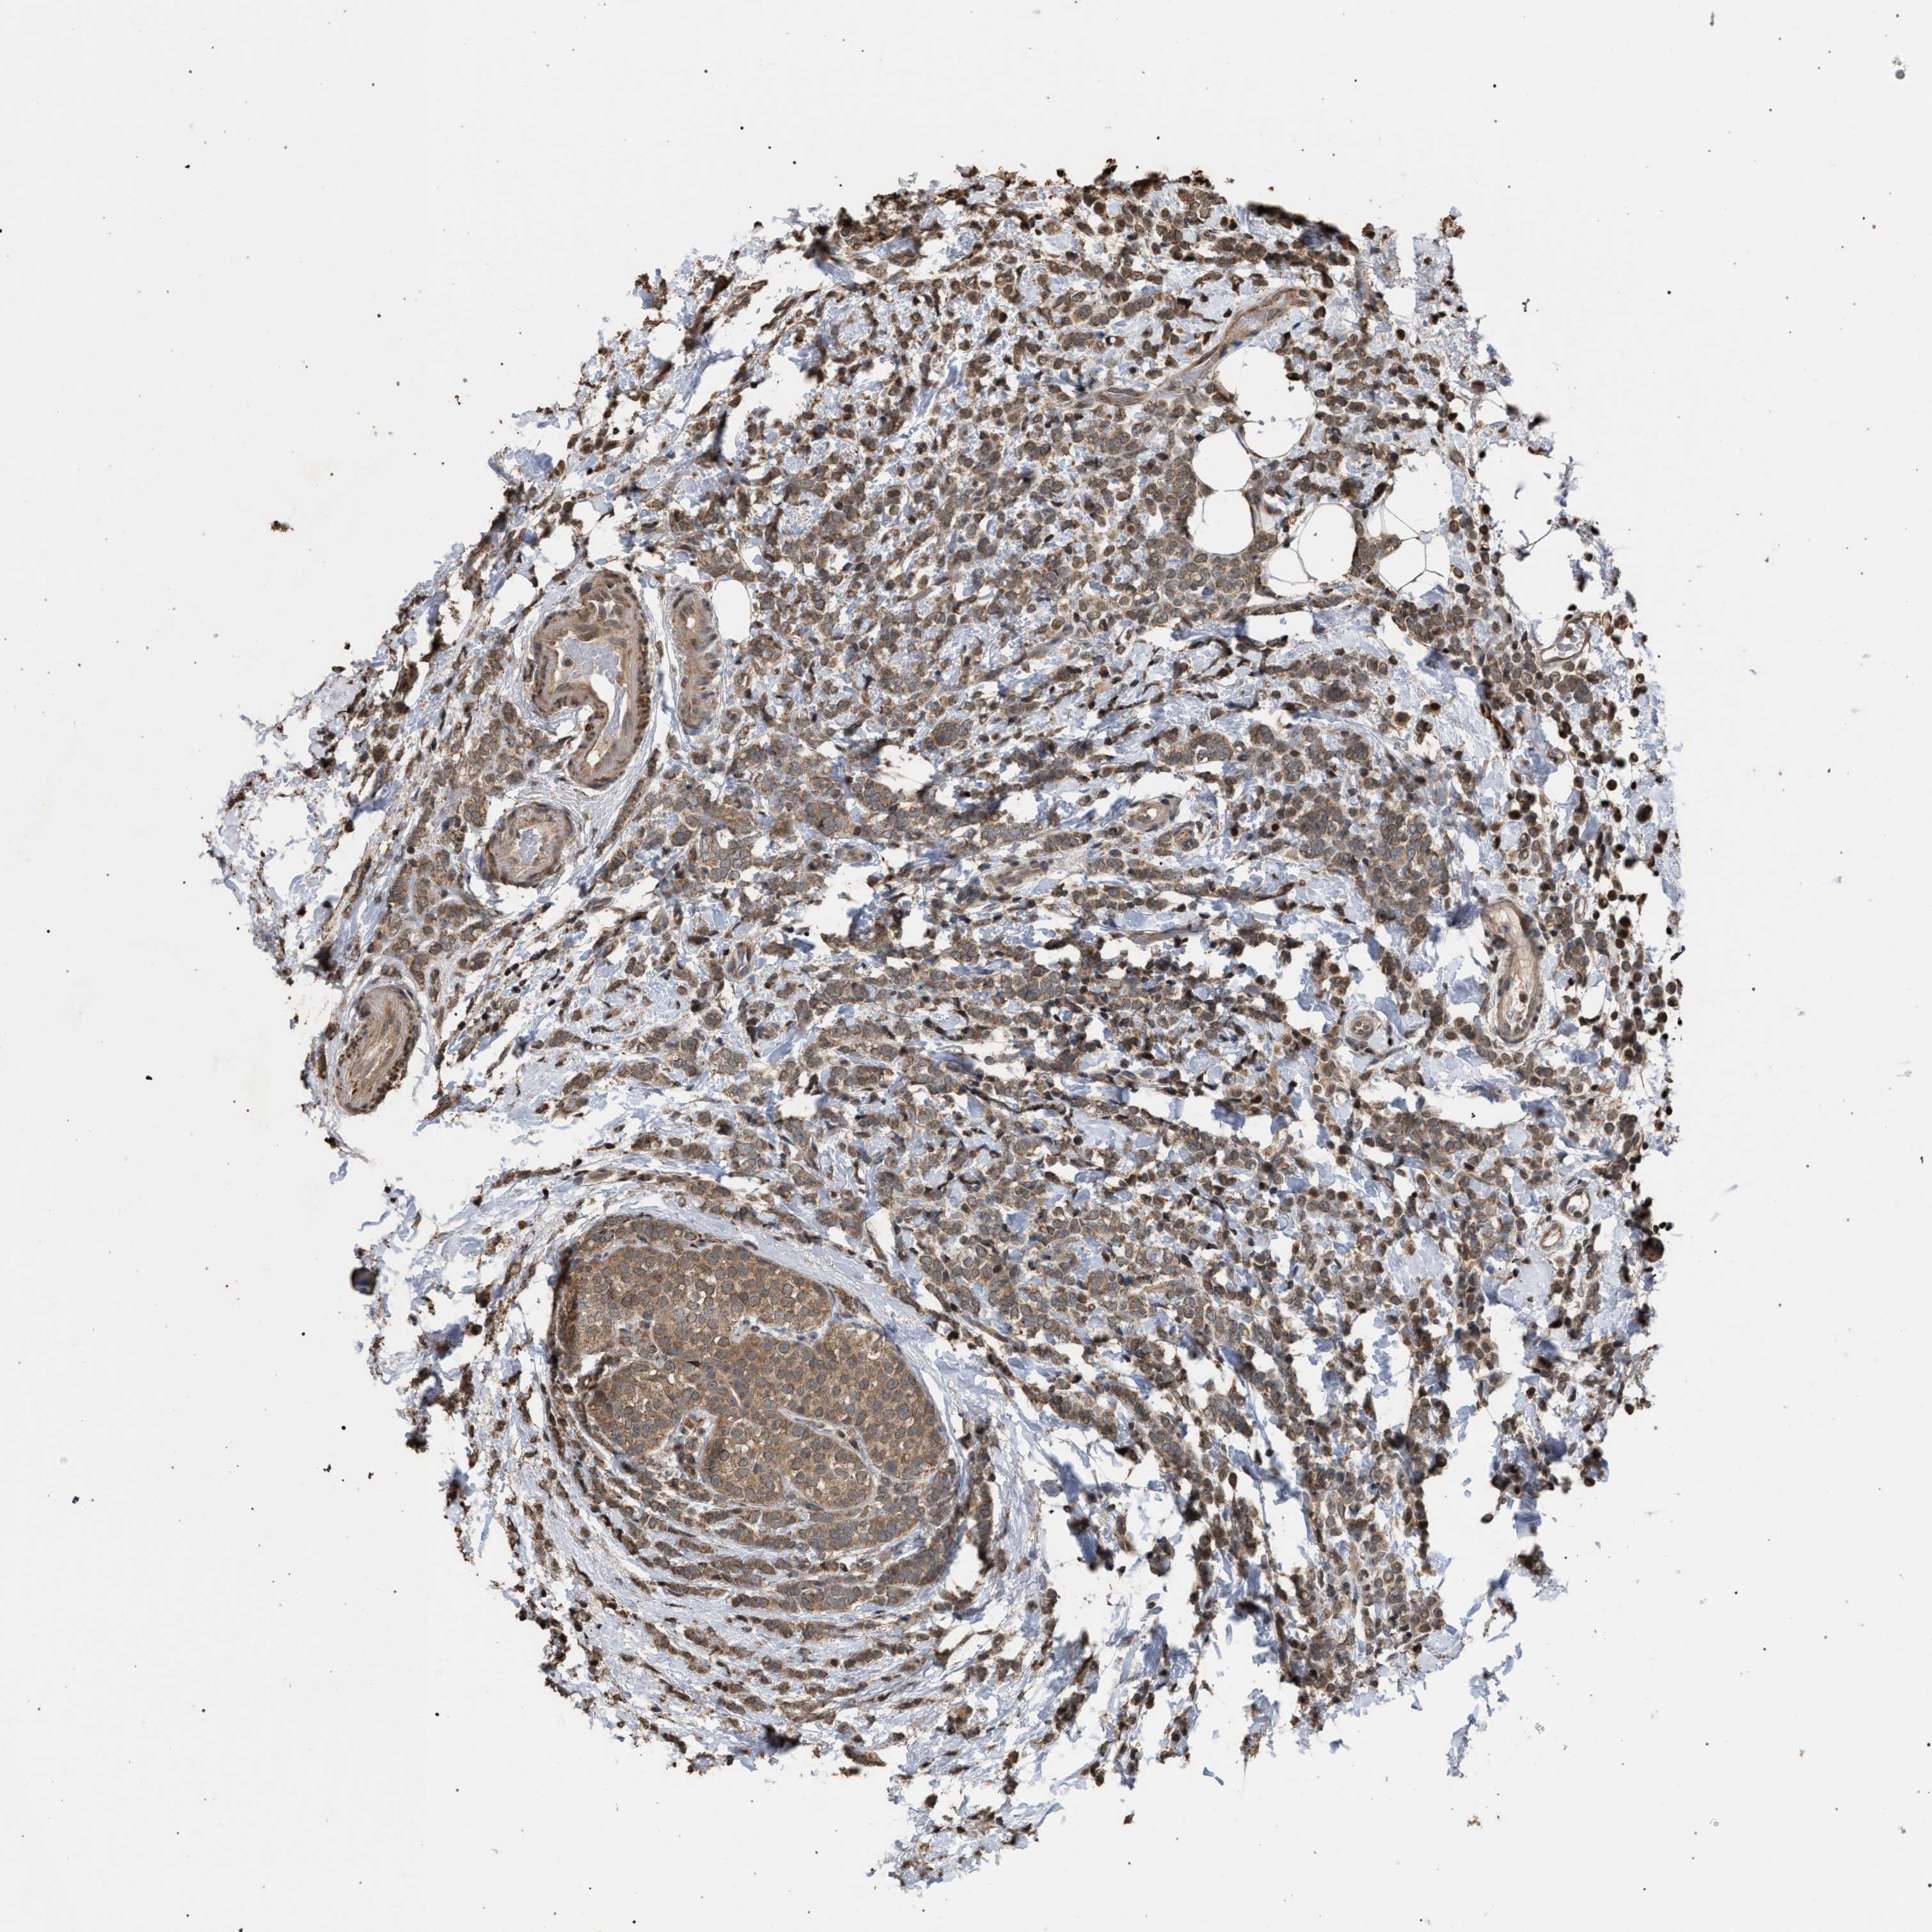

CANCER BREAST CANCER Show tissue menu

BRCA TCGA BRCA VALIDATION PROTEIN EXPRESSION